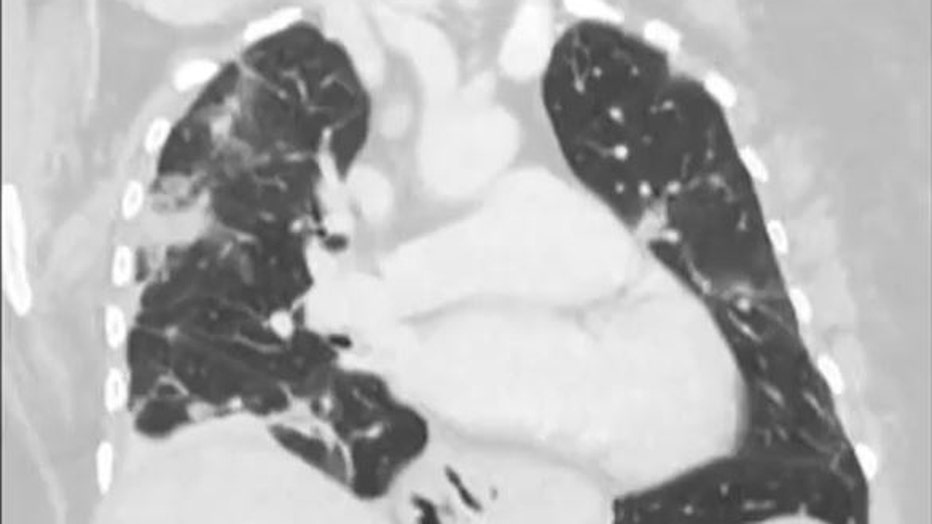

A year earlier, she had been admitted to her local hospital in southeast New South Wales state with symptoms including abdominal pain, diarrhea, a dry cough and night sweats.